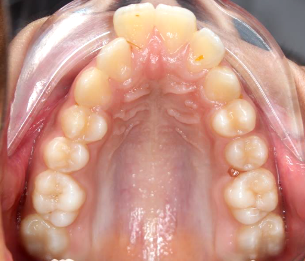

Fig.4 Bone- tooth anchored design: 2 anterior TADs 2 posterior TADs and support of molars